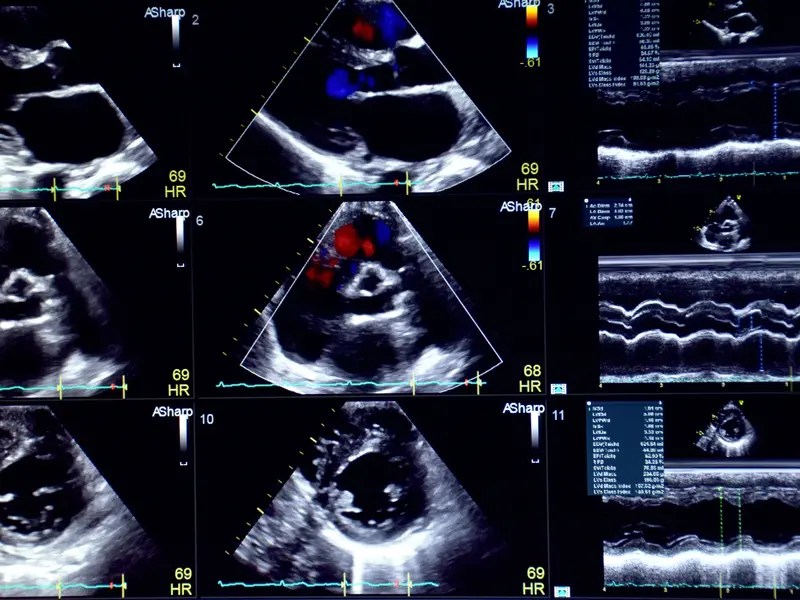

What Do Colors Mean In Echocardiogram . Find out what abnormal color patterns may indicate and when to. This part of the test shows blood flowing in your heart in color. Sensors attached to the chest and. This simplifies the interpretation of the doppler method. By analyzing these colors, doctors can assess the. Learn about the different colors seen on an echocardiogram and their significance. An echocardiogram uses sound waves to show how blood flows through the heart and heart valves. Traditionally, flow towards the transducer is red, flow away from. It helps your doctor more easily spot leaking heart valves as well as any other blood flow changes you. The colors on an echocardiogram represent the direction and velocity of blood flow within the heart. With color doppler, different colors are used to designate the direction and quantity of blood flow. Cfm uses measurements of the velocity and direction of blood flow to superimpose a color pattern onto a section of a 2d image (see figure 4). Review of color doppler in echocardiography, including technique, clinical use, strengths, limitations and comparison to pulsed and continuous doppler.

Learn about the different colors seen on an echocardiogram and their significance. It helps your doctor more easily spot leaking heart valves as well as any other blood flow changes you. Review of color doppler in echocardiography, including technique, clinical use, strengths, limitations and comparison to pulsed and continuous doppler. With color doppler, different colors are used to designate the direction and quantity of blood flow. Find out what abnormal color patterns may indicate and when to. The colors on an echocardiogram represent the direction and velocity of blood flow within the heart. Traditionally, flow towards the transducer is red, flow away from. This simplifies the interpretation of the doppler method. Cfm uses measurements of the velocity and direction of blood flow to superimpose a color pattern onto a section of a 2d image (see figure 4). By analyzing these colors, doctors can assess the.